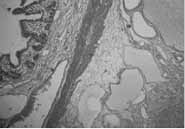

Un paciente de 5 meses de edad se presentó con cuadro clínico de tres días de evolución de vómito, inicialmente alimentario, que luego se tornó bilioso, asociado a ausencia de deposición. En el examen físico se apreció un abdomen blando con peristaltismo presente, pero disminuido, y sin masas palpables. La radiografía simple de abdomen mostró dilatación de asas delgadas y presencia de niveles hidroaéreos, hallazgos sugestivos de obstrucción intestinal mecánica (Figura 1). La ecografía abdominal fue reportada como sugestiva de obstrucción intestinal sin que se apreciaran masas. Con este diagnóstico de obstrucción intestinal mecánica se decidió practicar una laparotomía exploratoria en la que se encontró un quiste de 5 cm de diámetro, con contenido quiloso, localizado a 10 cm de la unión duodeno yeyunal, que causaba compresión del asa intestinal (Figura 2). Se practicó seguidamente una resección intestinal y una anastomosis termino-terminal. El informe de patología mostró una dilatación marcada de vasos linfáticos y quistes que comprometían desde la submucosa hasta el mesenterio, con contenido proteináceo y presencia de histiocitos espumosos, hallazgos compatibles con un quiste quiloso (Figura 3). La evolución del paciente en el postoperatorio fue satisfactoria.

Figura 3. Vista de la histología

Dentro del diagnóstico diferencial se incluyen lipomas, liposarcomas mesentéricos, tumores retroperitoneales, teratomas, tuberculosis abdominal y abscesos. El estudio anatomopatológico macroscópico muestra quistes uniloculares o multiloculares con contenido quiloso en su interior; microscópicamente se aprecian espacios anastomóticos de varios tamaños, que pueden estar separados por septos de endotelio y tejido linfático, incluso con tejido muscular y células inflamatorias en estos septos3.